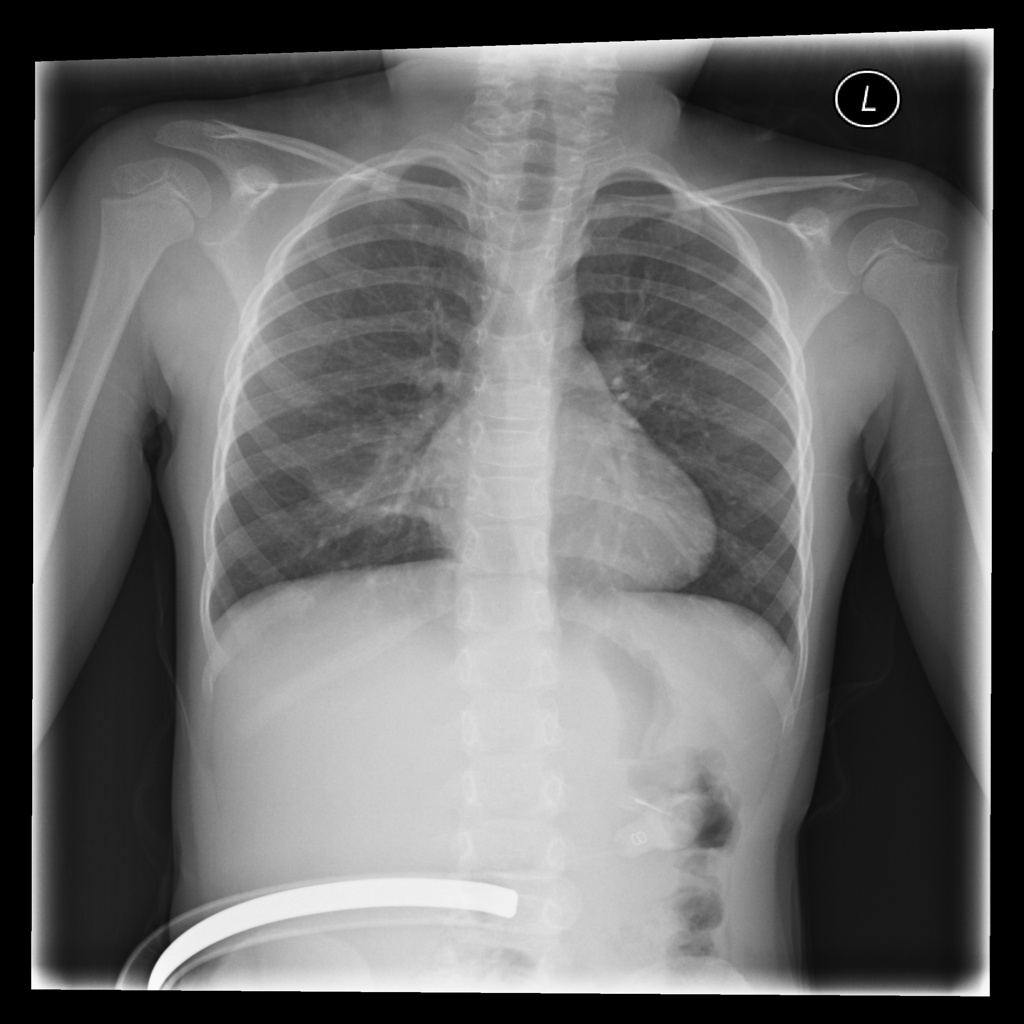

MedVistaGym comprises a set of verifiable medical VQA tasks that demand grounded, multi-step reasoning over visual inputs and intermediate evidence. These tasks span diverse diagnostic scenarios, including clinical perception, lesion-level evidence localization, subtle abnormality detection, and diagnosis-oriented evidence aggregation, where generating reliable answers requires calling external tool support. The training data in MedVistaGym is organized along two complementary axes. (1) Radiology VQA, covering cross-sectional and projection imaging, includes VQA-RAD Lau et al. (2018), which focuses on anatomy and finding recognition in X-ray, CT, and MRI images, and SLAKE Liu et al. (2021), a knowledge-aware dataset with clinically grounded questions over diverse radiology images. (2) Pathology VQA, covering microscopy and histopathology, includes PathVQA He et al. (2020), which emphasizes cellular morphology and tissue patterns. More details are provided in Appendix A.2.